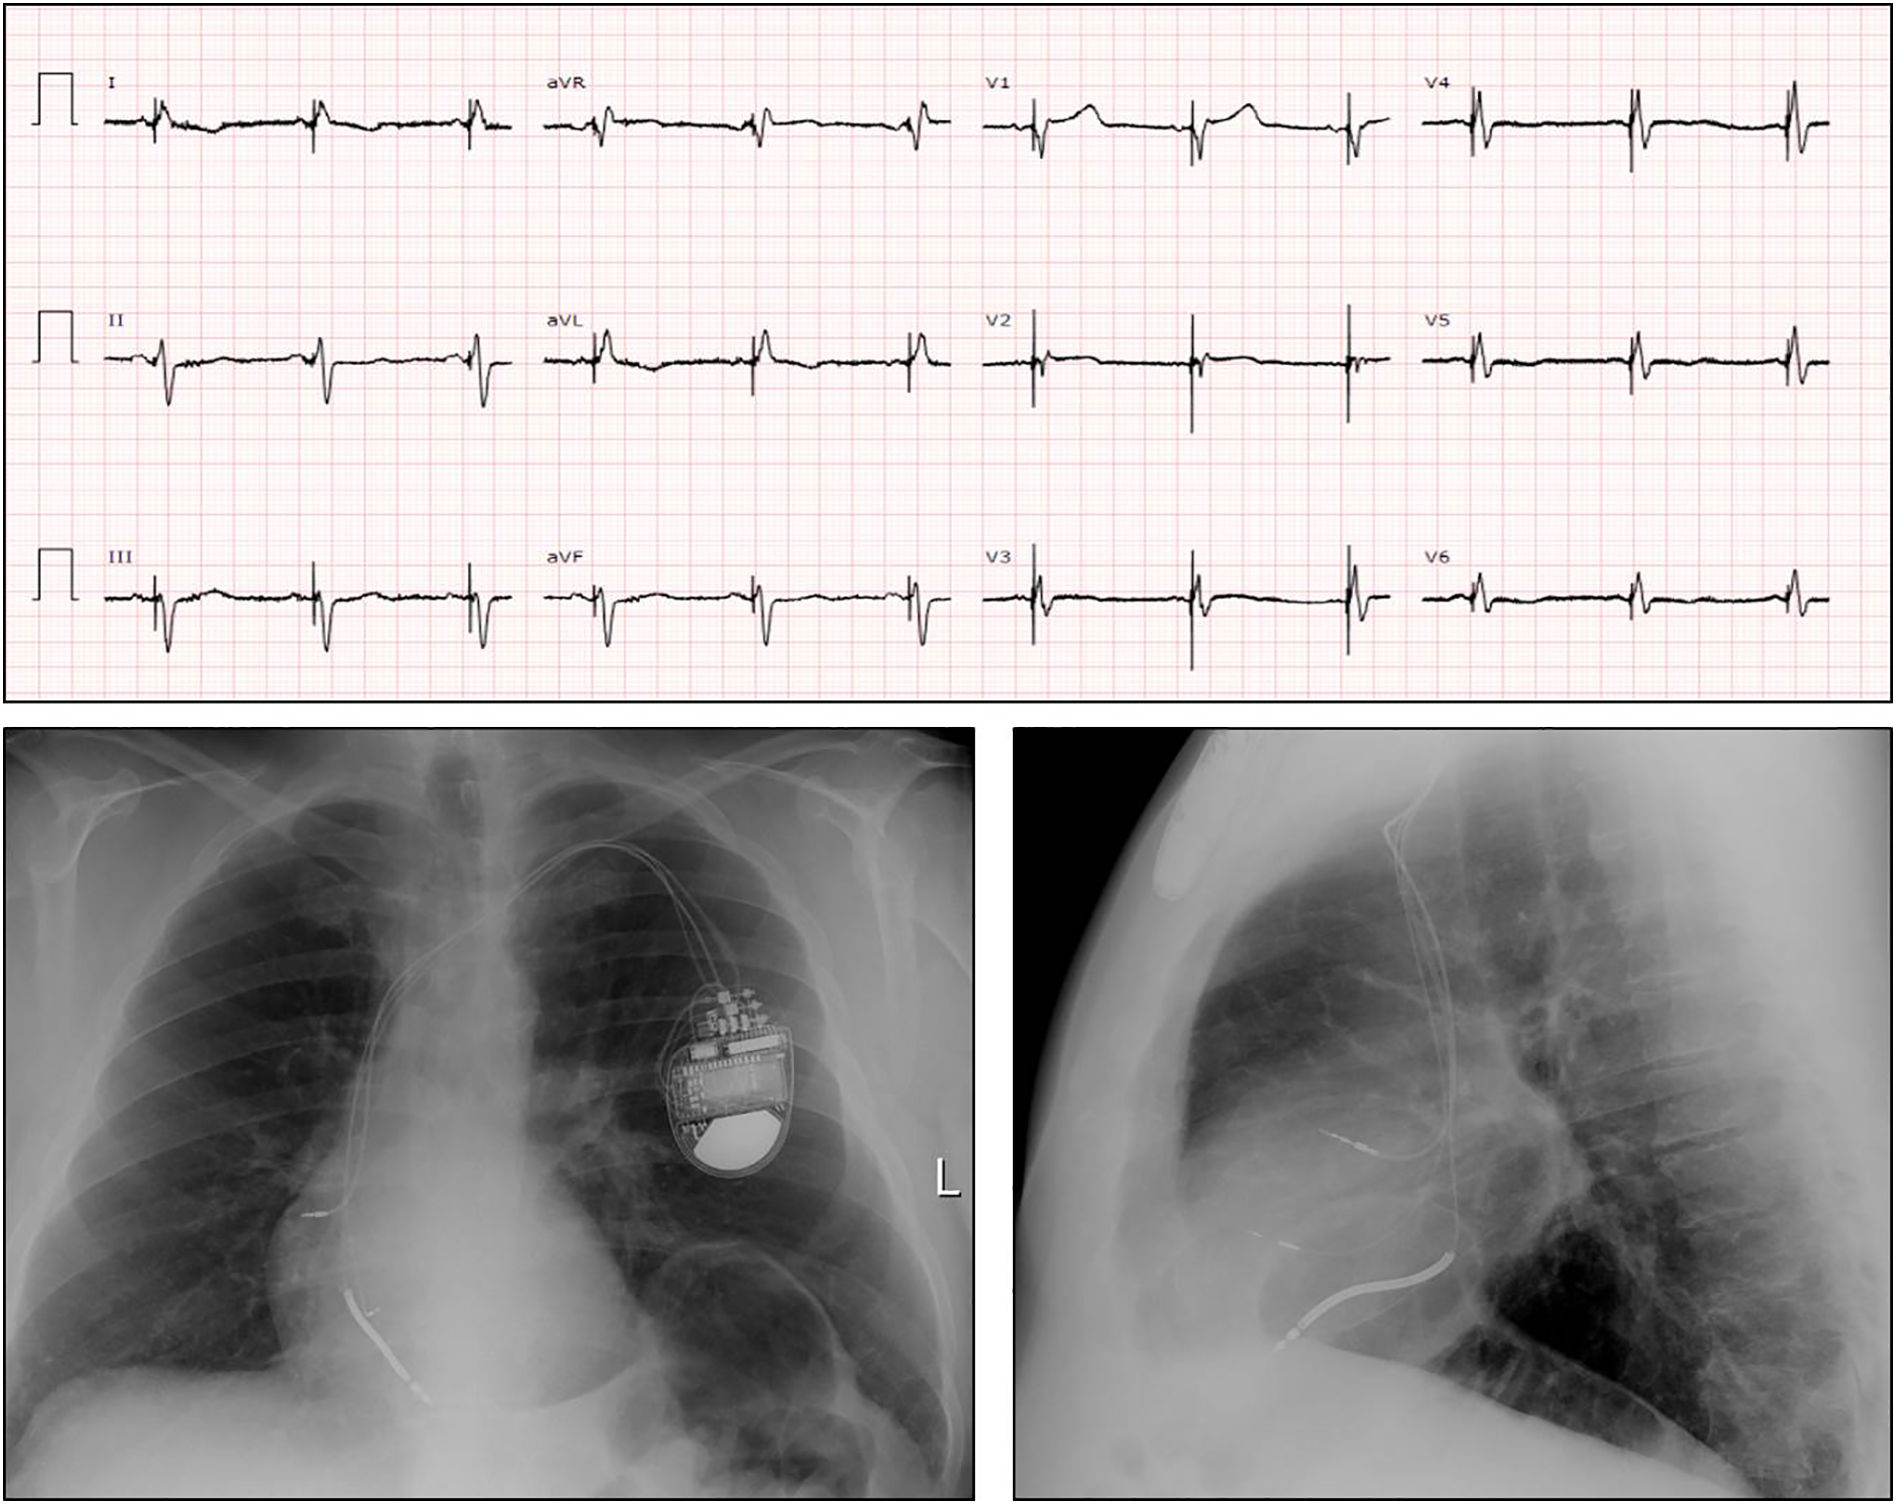

Panel superior: ECG postimplante de electrodo de estimulación en área de rama izquierda de haz de His. Es destacable la reducción de la anchura de QRS hasta 136 ms, la presencia de r´en V1 y un tiempo de activación ventricular en V6 de 62 ms que indican captura de la rama izquierda. Panel inferior: radiografía de torax en posición anteroposterior y lateral donde se observa el electrodo del marcapasos en la región del septo ventricular.

Un varón de 56 años portador de un desfibrilador implantable por cardiopatía isquémica y depresión importante de la función sistólica ventricular izquierda (FEVI: 21%) ha sido remitido para upgrade a estimulación biventricular, por el empeoramiento de su clase funcional (NYHA III) bajo tratamiento médico optimizado. El ECG mostraba ritmo sinusal con BRDHH y QRS: 180 ms (fig. 1). No se visualizó una adecuada vena tributaria del seno coronario por lo que se implantó un electrodo en el área de la rama izquierda/septal profunda en puerto de VI. El ECG postestimulación mostró un QRS estimulado de 135 ms con r´en V1 y tiempo de activación ventricular en V6 de 62 ms (fig. 2). Al cabo de 2 meses, la FEVI por ecocardiografía fue de 27% y el paciente ha mejorado su clase funcional (NYHA II).